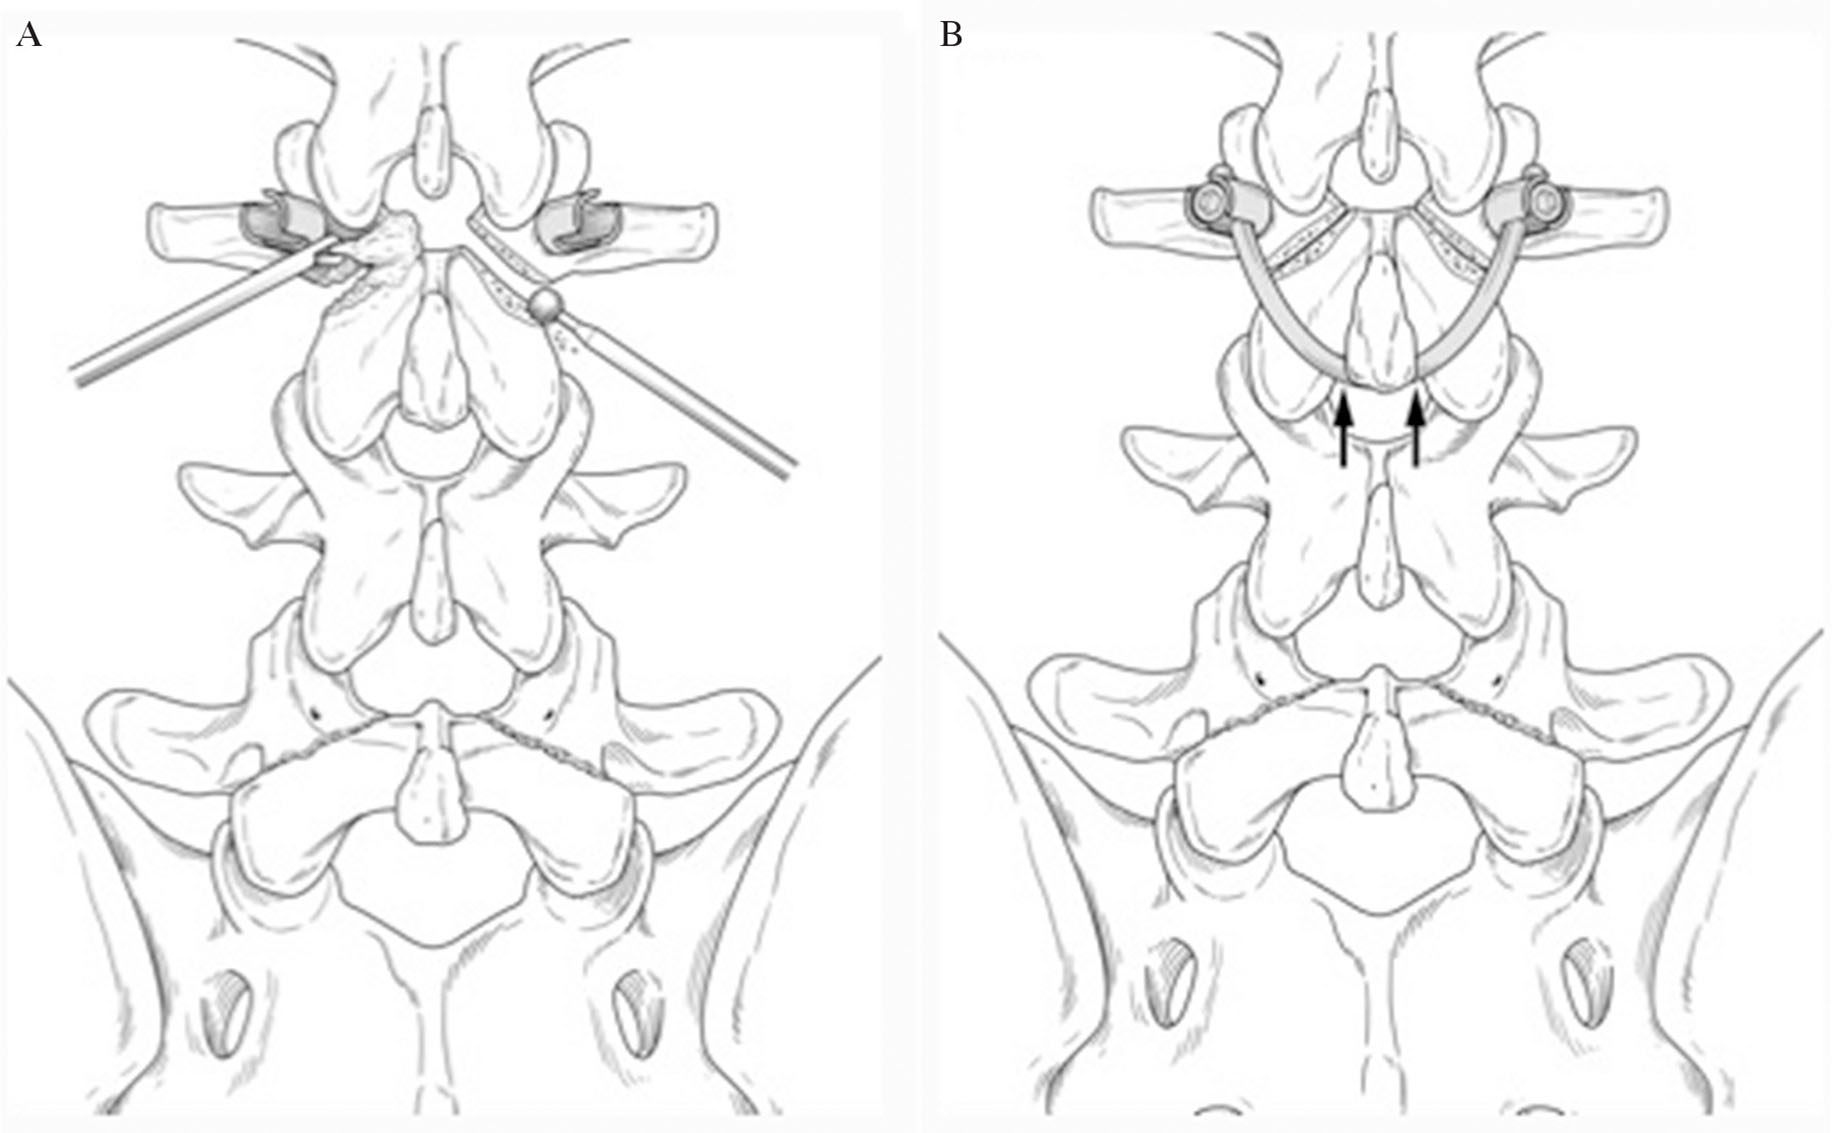

SurgeryOf several reported methods of direct repair, the smiley face rod method was adopted.13) A 7-cm midline skin incision was made, and the paraspinal musculature was retracted laterally to expose the bilateral L3 lamina, pars interarticularis, and transverse process. Using anatomic landmarks and fluoroscopic guidance, a starting hole for the pedicle screw was burred, the hole was tapped, and bilateral multiaxial pedicle screws were inserted (Fig. 3A). The pars interarticularis defect and osteophyte around it were exposed. Using a diamond surgical bur and curette, the osteophyte and synovium of the pseudarthrotic part of the spondylolytic segment was removed to refresh the defects. Cancellous bone was harvested from the iliac crest and placed in the defect before screw insertion. A 100-mm-long rod was bent to fit and placed immediately caudal to the L3 spinous process. The loose lamina was fixed more firmly after the bent rod was bumped against the spinous process using a rod pusher (Fig. 3B). Cancellous bone was implanted into the pars defects (Figs. 4A and 4B).

Illustration of the surgical procedure. The defect of the L3 pars interarticularis was exposed and curetted, then refreshed using a diamond burr. (A) Bilateral L3 pedicle screws were inserted. (B) When the bent rod was bumped against the spinous process using a rod pusher, the loose lamina was firmly fixed.